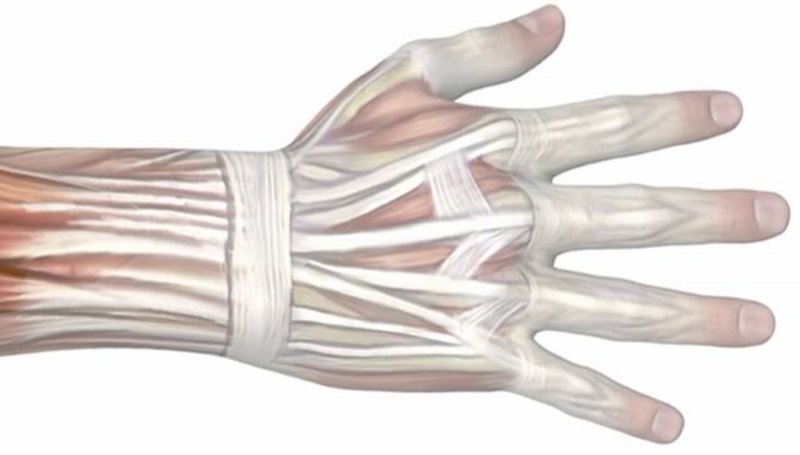

Poškodbe rok sodijo med najpogostejše poškodbe. Odprte poškodbe, kjer je prisotna rana na koži so nevarnejše od zaprtih, saj je rana vstopno mesto za bakterije, ki lahko povzročijo vnetje. Pri vreznih in vbodnih ranah, velikost rane na koži običajno ni sorazmerna s poškodbo globje ležečih struktur. Zmečkanine in raztrganine nastanejo zaradi delovanja večjih sil in pogosto so prisotne vrzeli tkiv, ki jih je potrebno nadomestiti. Amputacija pomeni, da je del telesa v celoti ločen od amputacijskega krna.